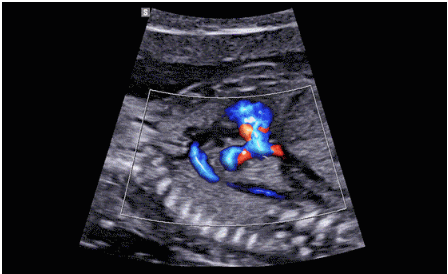

CrystalLive?是三星最新的超聲成像引擎,同時(shí)增強(qiáng)了2D圖像處理能力、3D渲染能力和彩色信號處理能力,能夠在復(fù)雜情況下提供出色的圖像性能,具備檢測外周血管、微循環(huán)血流的能力。